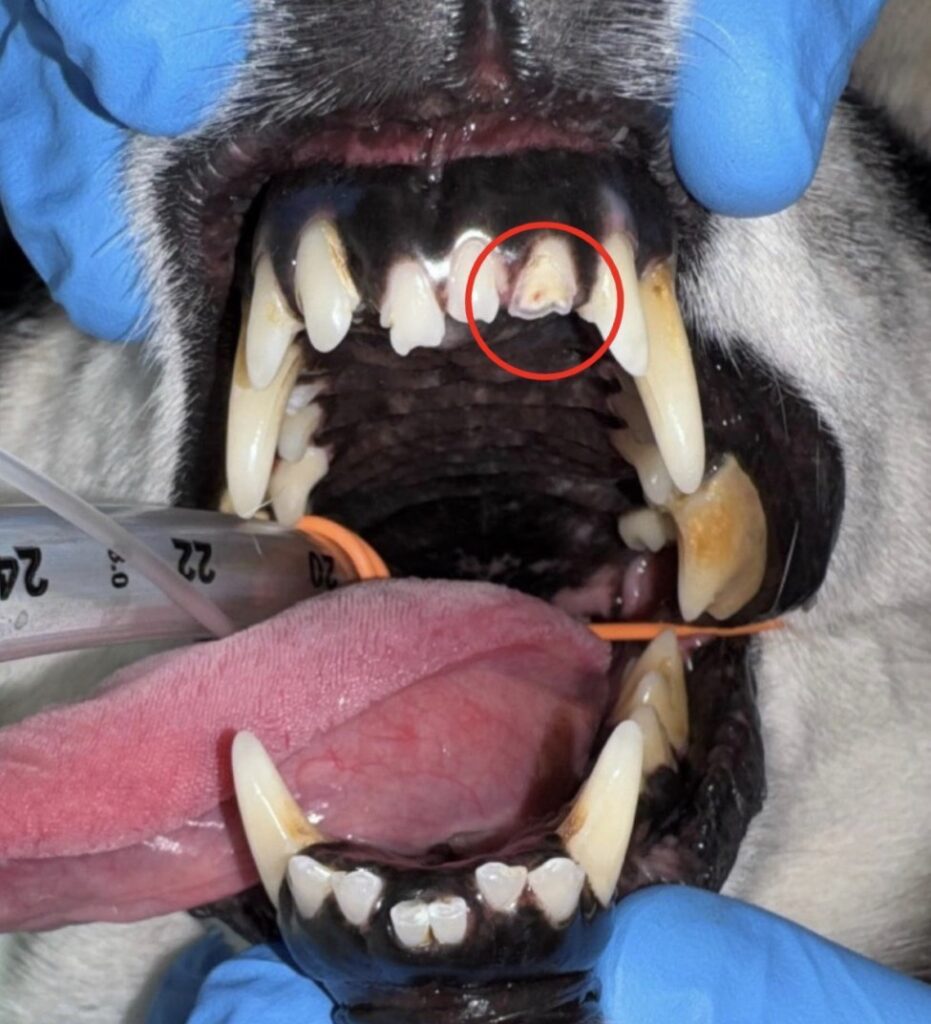

左上顎第4前臼歯では歯根破折、左上顎第2切歯では破折(露髄)が認められました。

破折(露髄)